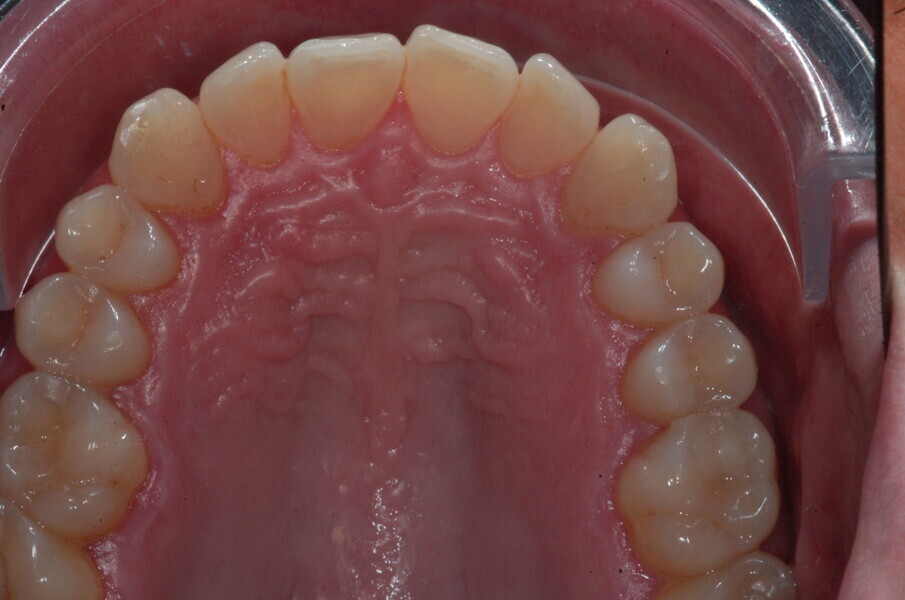

Le motif principal de consultation de ce patient âgé de 37 ans, était de rétablir l’alignement des dents antérieures sur les deux arcades. L’analyse faciale a indiqué une face courte avec un profil plat, mais une projection normale du menton (Figs. 9–12), et l’examen clinique a révélé une classe squelettique de type I (angle ANB = 0,89°) et une malocclusion de classe I avec supraclusion sévère (près de 100 %), une courbe de Spee très prononcée, un torque normal de l’incisive centrale supérieure (Ui-FH = 110°), un encombrement dentaire léger sur l’arcade maxillaire et modéré sur l’arcade mandibulaire (Figs. 13–18). Chez ce patient, les composantes de la supraclusion correspondaient à une dysmorphie squelettique grave correspondant à une hypodivergence (FMA = 14,24°), avec une inclinaison normale des incisives supérieures et inférieures et un angle goniaque réduit (110,46°). L’analyse du cliché céphalométrique indiquait une hauteur réduite de l’étage inférieur de la face associée à l’hypodivergence (Fig. 19). La seule option de traitement envisagée était un traitement orthodontique par aligneurs avec tous les éléments auxiliaires décrits (rampes d’occlusion, zones de pression, nivellement de la courbe de Spee dans les trois dimensions, élastiques de classe II et puissants contacts occlusaux) afin de corriger la supraclusion.

Le plan de traitement numérique (ClinCheck) avait prévu douze aligneurs pour l’arcade maxillaire et dix-sept pour l’arcade mandibulaire. Les objectifs du traitement visaient à combiner les mouvements verticaux d’extrusion des dents postérieures et les mouvements d’intrusion des dents antérieurs, au moyen de rampes d’occlusion, tout en utilisant des taquets d’extrusion pour assurer la désocclusion des dents postérieures et l’intrusion des dents antérieures inférieures, nécessaires au nivellement de l’arcade mandibulaire. La courbe de Spee a été nivelée et le profil plat ainsi que la position des lèvres ont été améliorés par une vestibulo-version des incisives supérieures et inférieures. Le plan avait prévu des élastiques de classe II pour faciliter la vestibulo-version des dents inférieures et les puissants contacts occlusaux postérieurs, avec une extrusion relative des dents postérieures. Une morphologie plus large de l’arcade et une intercuspidation idéale ont été obtenues par des mouvements de torque proches de 0° des dents latérales et postérieures supérieures. Aucune conception technique excessive n’avait été prévue dans le plan de traitement numérique. En raison de l’âge du patient, les aligneurs ont été changés tous les dix jours, dans le cadre d’un traitement d’une durée inférieure à six mois. À la fin de la première série d’aligneurs (Figs. 20–24), un nouveau plan de traitement numérique comportant cinq autres aligneurs a été conçu, en vue d’améliorer l’intercuspidation des molaires sans élastiques. La durée totale du traitement a donc été prolongée jusqu’à 7,5 mois puisque les aligneurs supplémentaires étaient changés toutes les semaines.